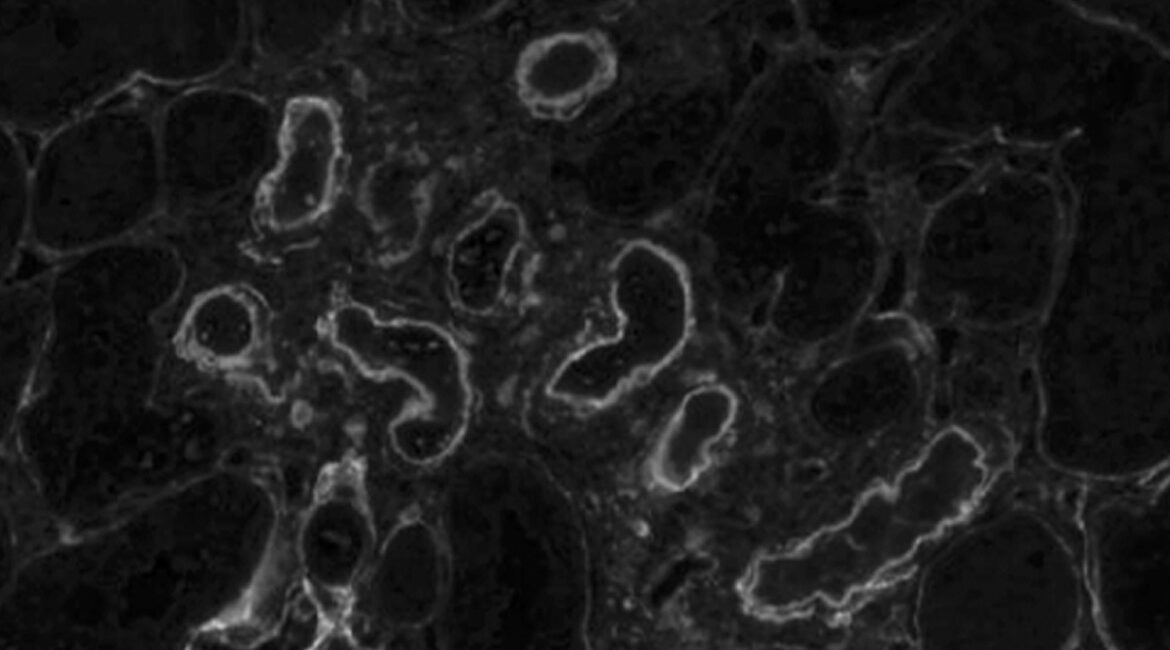

Integratives Endotyping der IgA-Nephropathie

Bis zu zehn Prozent aller Menschen in Deutschland leiden an einer chronischen Nierenerkrankung. Da die Niere eine zentrale Rolle in der ...

Die begrenzten Therapieoptionen in der Nephrologie und der Mangel an therapeutischen Innovationen unterstreichen die ...

Ursachenforschung für Nierenerkrankung bei Kindern

Dank der Entwicklung zahlreicher neuer Medikamente und einer verbesserten Diagnostik können heute nierenkranken Kindern eine Vielzahl ...